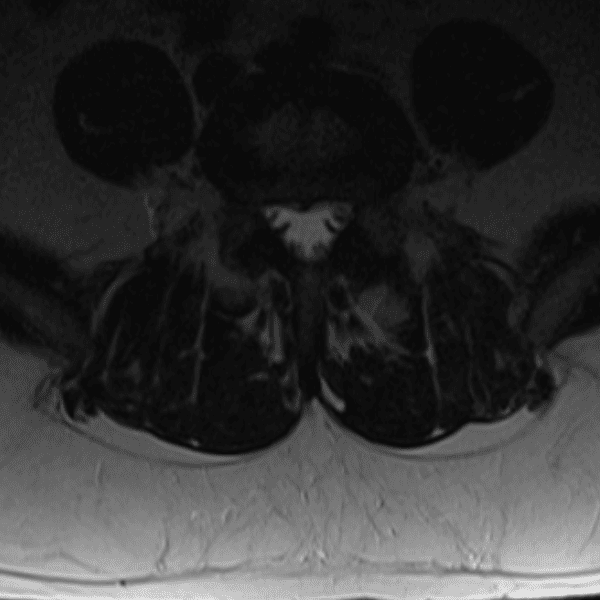

Simulates call by including subtle or difficult cases and some normals.

35 cases